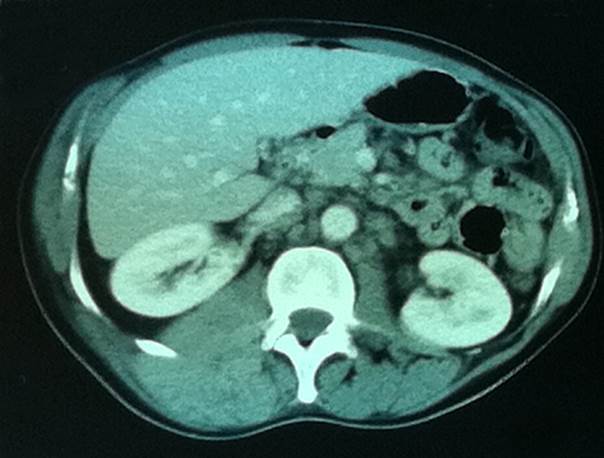

Para mayor aproximación diagnostica se realiza tomografía de tórax, abdomen y pelvis que observa: masa a nivel paraespinal derecha, compromiso óseo y muscular local engrosamiento pleural, moderado a severo derrame pleural derecho en cavidad libre(Figura 2).